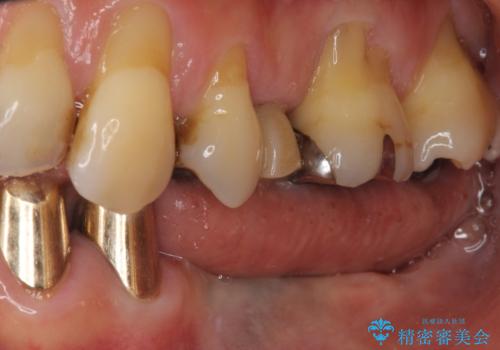

- 義歯を使いたくないものの、骨の幅が狭くインプラント治療を断られているとのことで来院された患者様です。

レントゲンやCTより、骨の高さと幅が不足しており、骨を増やす必要のある状態でした。

しかしながら、全身疾患により骨造成術の予後に不安があったため、デンサーバー(Densah ® Bur)という骨幅を増大することが可能なドリルを用いてインプラントを埋入することとしました。

入れ歯の支台となっていたコーヌスのゴールドも除去し、インプラント部と合わせてオールセラミッククラウンにて補綴治療を行うこととしました。